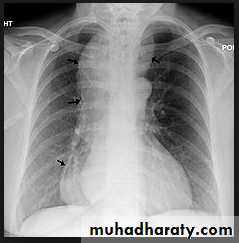

• Alveoiar oedema (‘Bat’s wings’)

• Kerlev B lines (interstitial oedema)

• Prominent upper lobe vessels

• Cardiomegaiy

• Pleura

• effusion

Kerley A lines (Arrows), Kerley B lines (arrowheads)